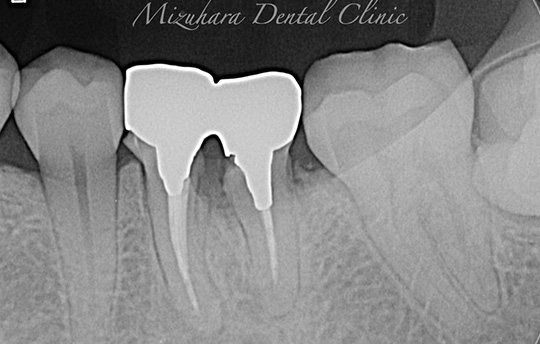

世界基準の成功率を目指した精密根管治療

根管治療

当院では豊マイクロスコープ、ラバーダムを使用し、世界基準の成功率を目指した精密根管治療による「歯を残す」ための治療をご提供します。